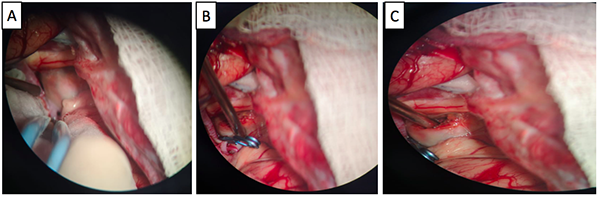

Paciente de género femenino, de 51 años de edad, que consultó a oftalmología por un cuadro clínico de 20 días de evolución consistente en disminución súbita de la agudeza visual del ojo derecho, no asociado a dolor, síntomas sistémicos, ni compromiso de los movimientos oculares. En la evaluación inicial se encontró en el ojo derecho un defecto pupilar aferente, agudeza visual mejor corregida de 20/400, discromatopsia con test de Ishihara 0/14, y excavación del 20% en el borde del disco óptico, compatibles con neuritis óptica retrobulbar. En la campimetría por confrontación, se encontró una hemianopsia temporal derecha. A su ingreso a urgencias se le realizó tomografía de cráneo en la que se encontró lesión selar y supraselar, por lo cual se solicitó RMN cerebral contrastada bajo la sospecha de un macroadenoma hipofisiario. En la RMN (Ver Imagen 1) se identificó lesión ovalada, de localización supraselar, con efecto de masa sobre el quiasma óptico y la porción cisternal de ambos nervios ópticos, principalmente del lado derecho, con cambios en secuencias de susceptibilidad, compatible con aneurisma de la AComA parcialmente trombosado.

Figura 1. RMN de cráneo en la que se identifica lesión sacular de localización supraselar con efecto de masa, mide 22 mm x 19 mm x 17 mm (A), desplaza y comprime el quiasma óptico y la porción cisternal de ambos nervios ópticos, especialmente el del lado derecho (B), tiene un área en forma de media luna que realza tras la administración del medio de contraste (B y C). En la parte inferior se observa la Arteriografía cerebral con un aneurisma sacular de contornos irregulares, localizado en el segmento comunicante anterior de 8mm x 6mm x 5 mm (D, E y F).

Para definir con mayor detalle la anatomía vascular, se realizó una arteriografía (Ver Imagen 1), con la que se confirmó la presencia de un aneurisma sacular de la arteria comunicante anterior, de contornos irregulares, de 8x6x5 mm, sin signos de ruptura con una orientación antero-inferior. Esta clara diferencia entre el tamaño de la lesión en la RNM y la arteriografía confirma la presencia de un trombo intra-aneurismal.